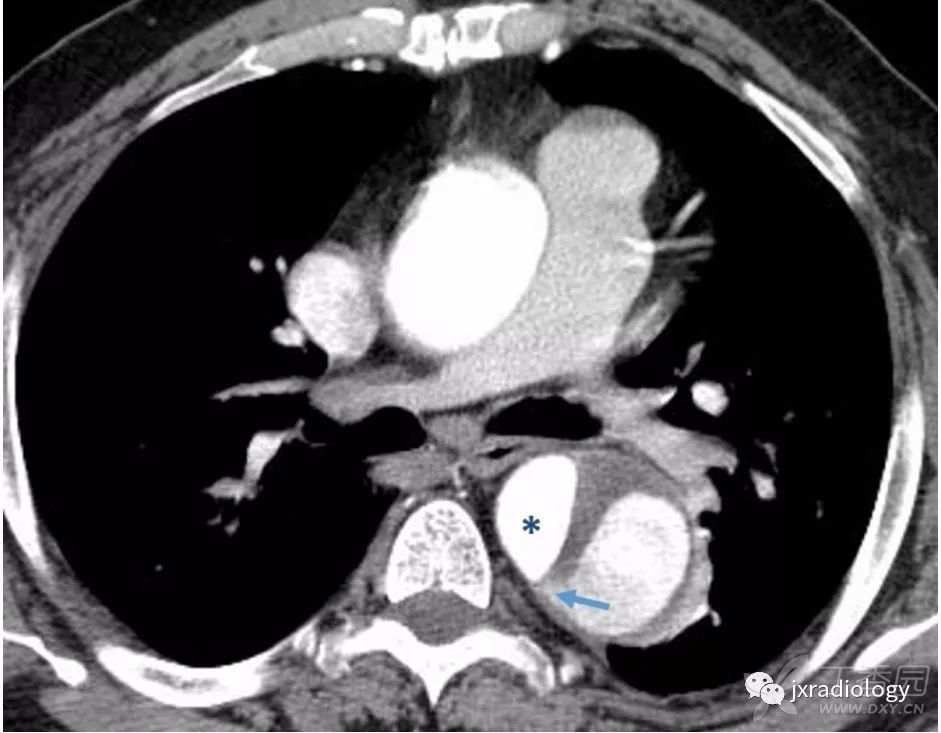

假腔通常显示较大的面积,与真腔相比呈延迟强化,并且可能显示在假腔边上出现-鸟嘴征(beak sign)( 图8 )

图8:鸟嘴征(箭头)代表假腔。

它是指在假腔内扩张的楔形血肿,因为它可以占据空间并分离内膜。真腔(星号)可通过其较小的管腔和早期强化来与假腔区分。